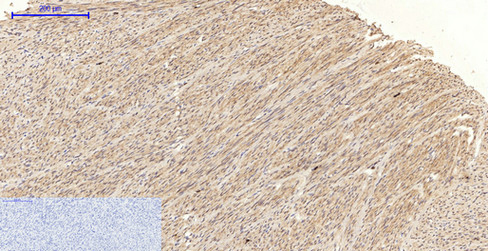

IHC (Immunohiostchemistry)

(Immunohistochemistry of paraffin-embedded Human uterus tissue with Phospho-JNK1/2/3 (Thr183/Y185) Polyclonal Antibody at dilution of 1:200)